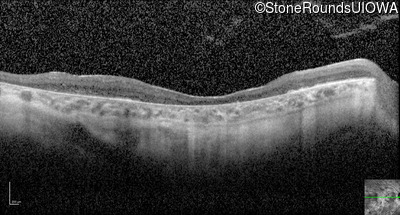

Optical Coherence Tomography - Left - 10/225

Exemplar / OCT Stack